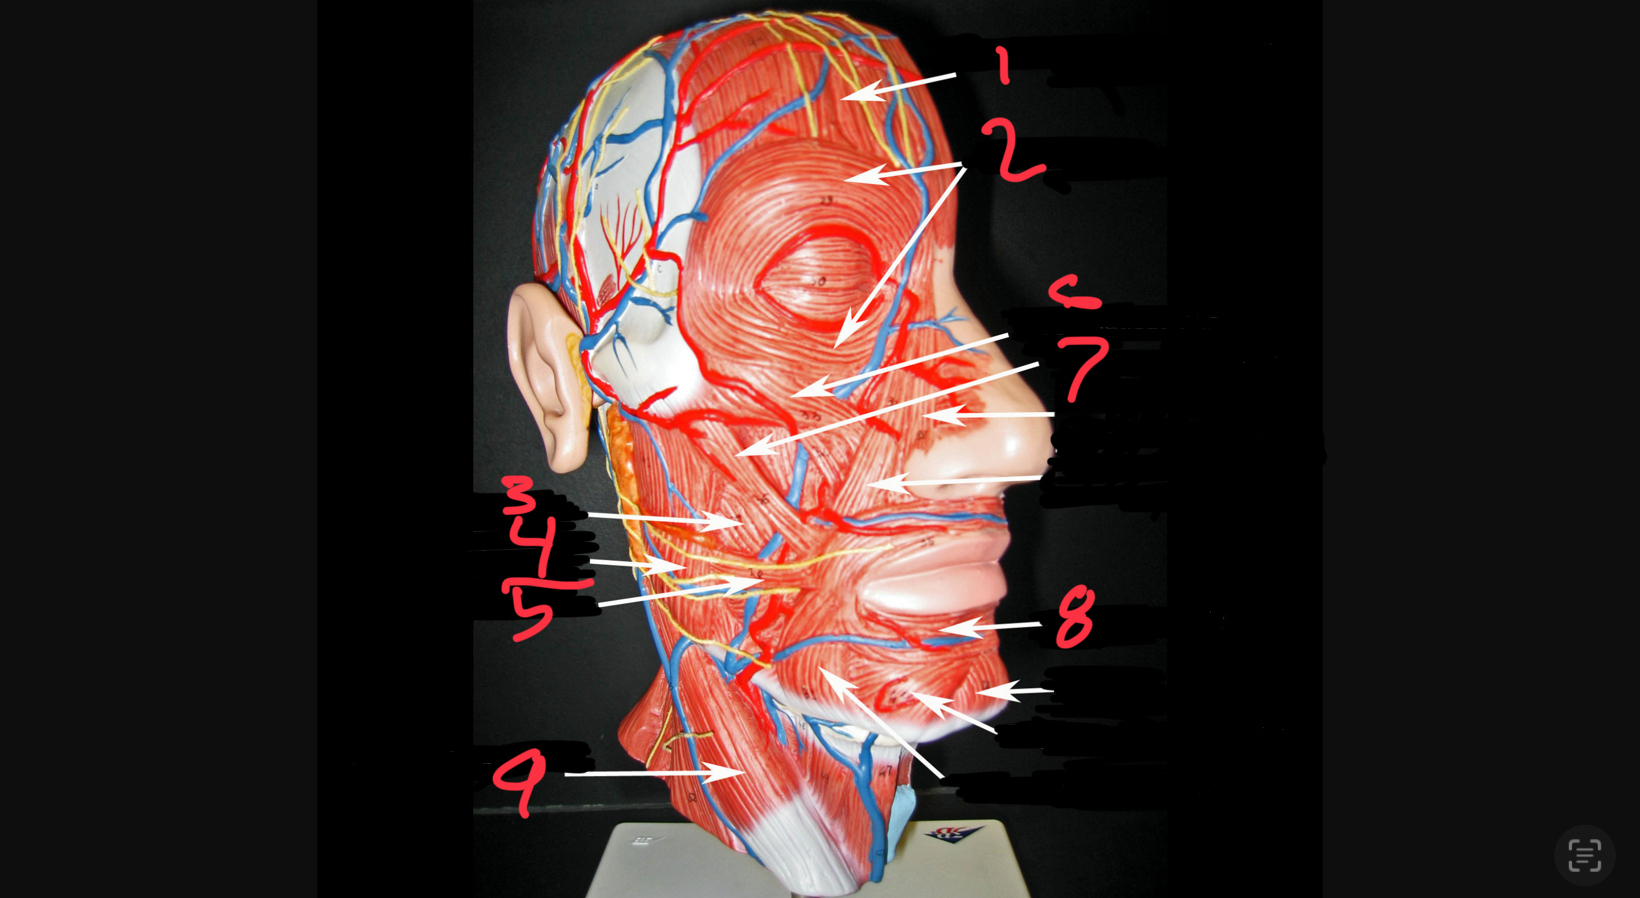

what #1

occipitofrontalis (frontal belly)

what is #2

orbicularis oculi

what is #3

buccinator

what is #4

masseter

what is #5

risorius

what is #6

zygomaticus minor

what is #7

zygomaticus major

what is #8

orbicularis oris

what is #9

sternocleidomastoid